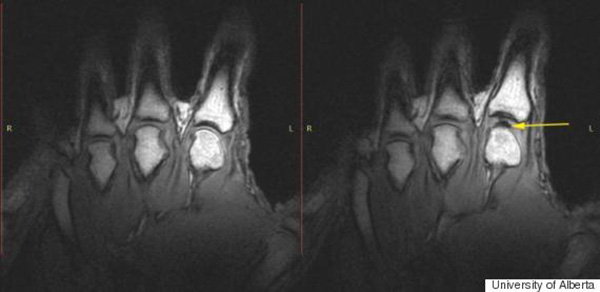

Khi bạn bẻ ngón tay, một khoảng đen xuất hiện.